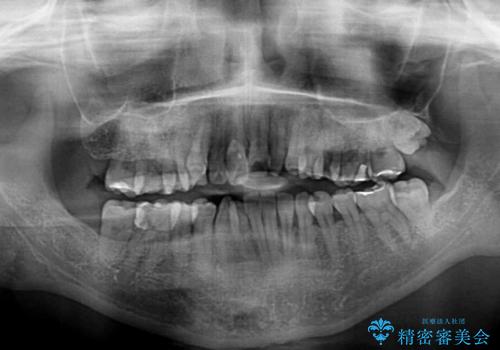

下顎骨が左側にズレて成長してしまったため、左側の咬み合わせが上下反対になっている状態でした。

骨格的なズレは歯列矯正のみでは改善できず、骨切除が必要となります。

そこまでの処置は望んでいらっしゃらなかったため、歯列矯正でのカムフラージュにより咬み合わせを改善することとしました。

予想通り左側の咬み合わせの調整に苦労をしましたが、最終的には違和感のない咬み合わせを達成することができました。